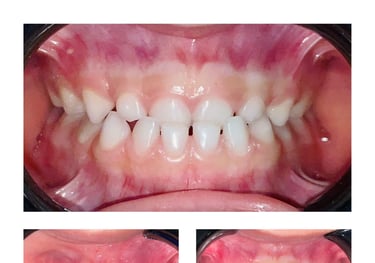

Odontopediatría

La odontopediatría es la especialidad dental dedicada a el cuidado, tratamiento y prevención de las lesiones bucales en niños y adolescentes. Nuestro enfoque es brindar un ambiente amigable y acogedor, adaptado a las necesidades de los pequeños pacientes, para asegurar una experiencia cómoda y libre de miedo. Ofrecemos controles preventivos, limpieza, tratamiento de caries, sellantes y orientación en hábitos de higiene bucal. En nuestra clínica, promovemos una sonrisa saludable desde temprana edad, formando buenos hábitos que perdurarán toda la vida.